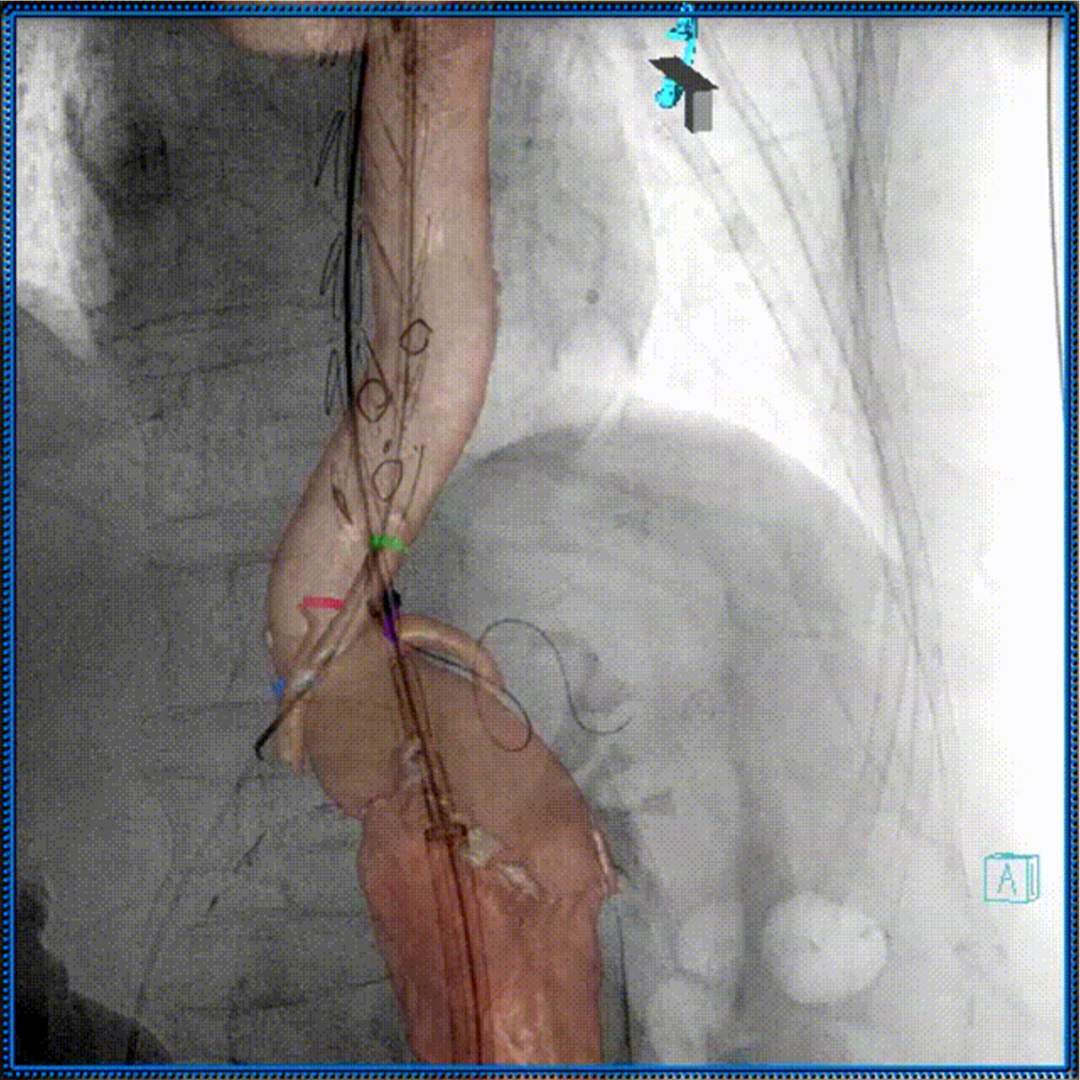

术中3D影像引导,主体支架精准定位

3D影像引导下,

主体支架窗口与弓上三分支开口对位

依次超选无名、左颈总及左锁骨下动脉

术后造影,支架形态良好,分支血流通畅